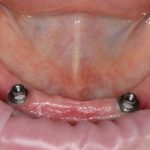

Помимо этого, один из этапов лечения периимплантита предполагает «превращение» субгингивального имплантата в трансгингивальный (подробности здесь>>). Описанную в статье методику можно считать успешной —  она, пусть и не восстанавливает уровень костной ткани вокруг имплантатов, но помогает избежать развития заболевания и потери имплантатов вообще:

То есть, если часть имплантата находится не в кости — в этом нет ничего страшного и предосудительного. Так почему нужно переживать из-за того, что имплантат вышел  за пределы костной ткани, пусть и в сторону верхнечелюстной пазухи?